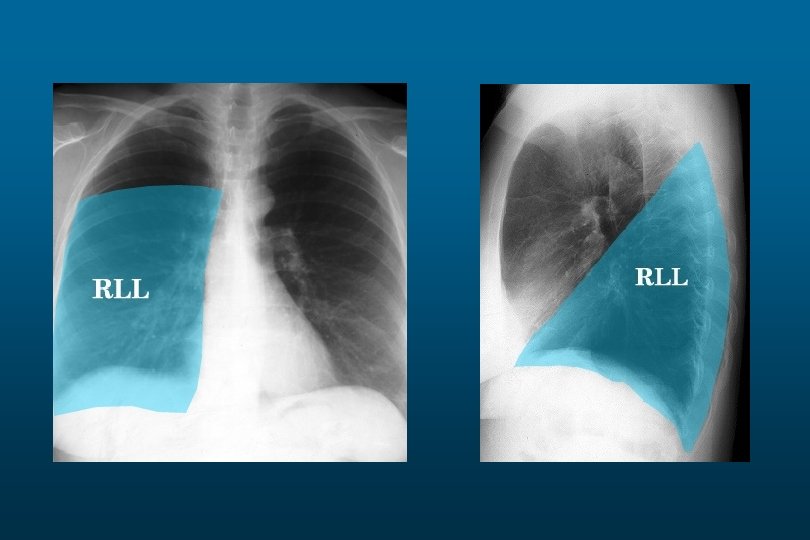

Right lower Lobe Pneumonia